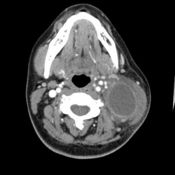

Lymphoma cancer is categorized two types namely Hodgkin’s lymphoma and non Hodgkin’s lymphoma. Both have the same kinds of treatments applicable anyway. So as far as non Hodgkin’s and Hodgkin’s lymphoma cancer treatment is concerned, there is nothing to debate about which cure is the best or which type of cancer is easily treated. Curing this cancer involves either surgery or a combination of surgery, radiotherapy and chemotherapy.

Surgery is the primary method to treat lymphoma cancer. Since lymphoma cancer is caused by a tumor, this lump can be only removed through surgical method. This is a lymphoma cancer treatment that helps you survive. It is the same initial lymphoma cancer treatment children can undergo to. As long as there is a mass, surgery is the only means to remove it. Removing the tumor is simply the key to survive from this cancer.